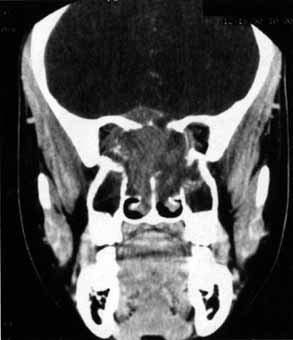

CRANIAL NERVE I (OLFACTORY NERVE)

Anosmia caused by damage of cranial nerve I may be a helpful symptom of ethmoid or sphenoid sinus tumors invading the orbit (Fig. 20).44 Olfactory groove meningiomas and esthesioneuroblastomas may also present with anosmia prior to developing vision loss.45 Trauma that involves the orbit and is associated with anosmia should be considered a basilar skull fracture with potential for cerebrospinal fluid leak until proven otherwise (Fig. 21).

Fig. 21 A 21-year-old man sustained a skull fracture from a motor vehicle accident 2 months prior to this examination. The patient describes anosmia since the accident. Computed tomography discloses a large medial wall orbital fracture extending through the cribriform plate (arrow). Orbital reconstruction was performed through a frontal craniotomy where dura was found incarcerated within the fracture. The orbital fracture was repaired by cranial bone grafting.